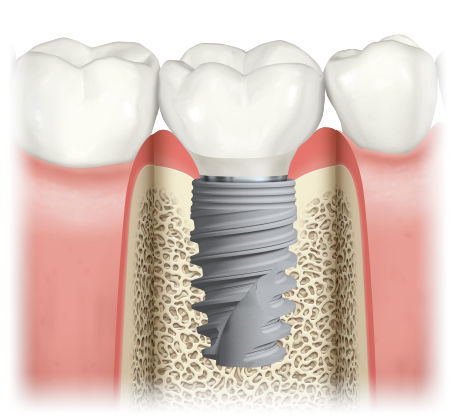

A Dental Implant can be defined as a surgical component which interfaces with the jawbone, in order to support the dental prosthesis such as a crown, a bridge or a denture. The major benefit of an implant is that it preserves neighbouring teeth and the jawbone, prevents jaw bone resorption, restores the missing tooth and the supporting structures, replaces it in such a way that it almost serves like a natural tooth, in form and function. It also retains your natural face shape and smile.

- Implants fuse to the jaw bone upon their placement and thereby look and act like your own natural teeth.

- Implants prevent the bone loss beneath the missing teeth and keep the bone intact.